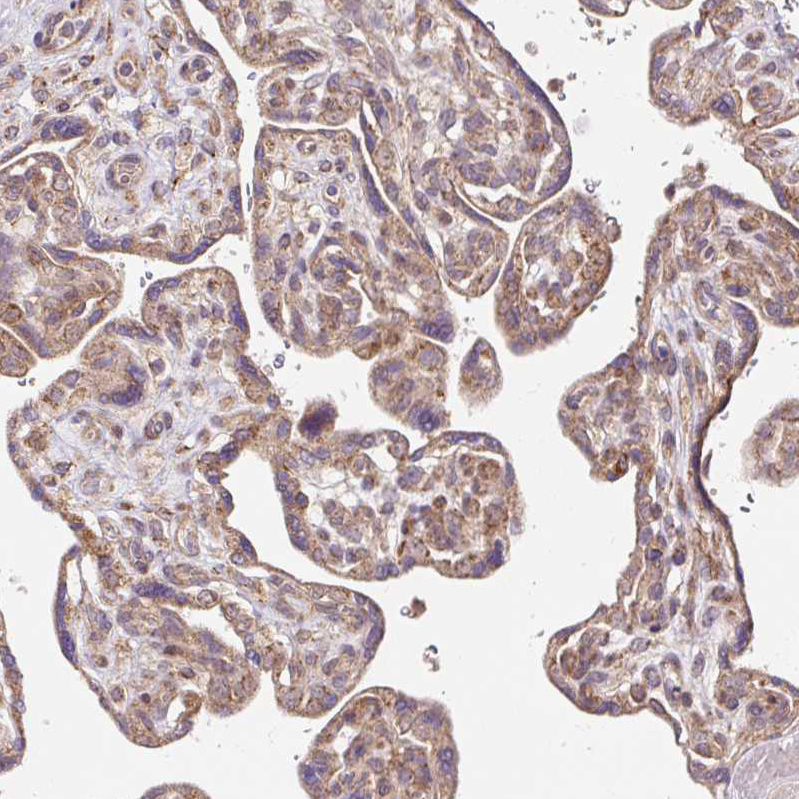

Immunohistochemical staining of human pancreas shows moderate granular cytoplasmic positivity in exocrine glandular cells.